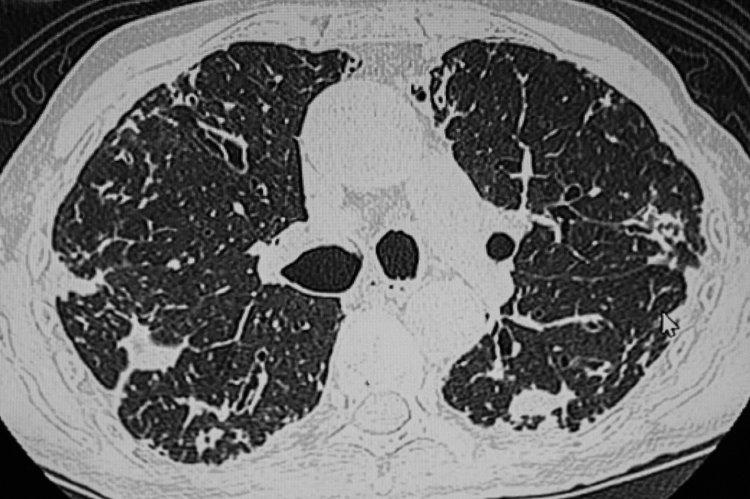

• 肺結節

肺結節是指肺部出現的≥3cm的病竈,在影像學裏表現爲密度增高的陰影。

中國醫學科學院腫瘤醫院山西醫院胸外科主任廉建紅指出,現在檢查儀器的精密度都很高,一些微小結節也能被及時發現,這些結節發現時大部分是比較早期的,無需過分緊張。尤其是8mm以下的結節,一般都建議以隨訪爲主。

建議年齡>45歲的成年人每年進行一次肺部CT檢查,通過檢查可及時發現早期潛在的問題,對防治結節有重要意義。